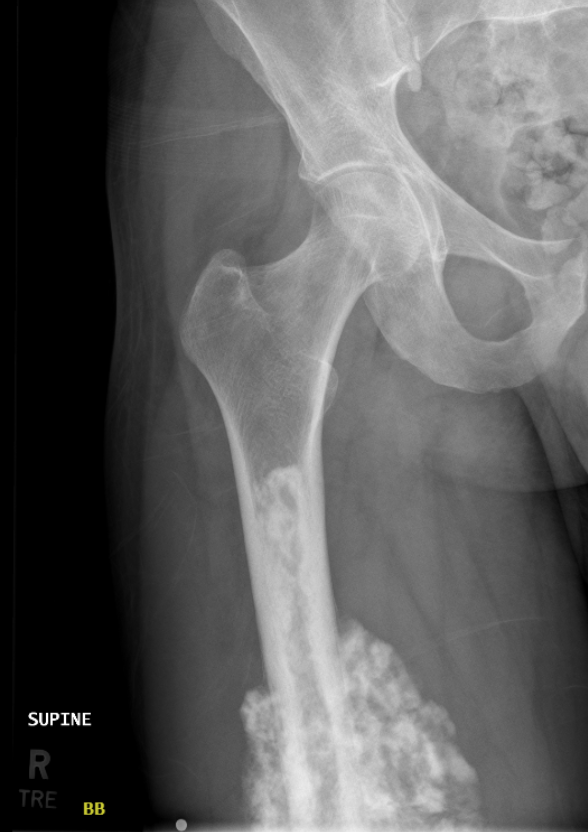

The preliminary x-rays showed visible cloudiness around my femur, an indicator of bone cancer, which prompted a frightening response by the doctors and I was referred to a team of Oncologists with the Utah Cancer Specialists. In the following two weeks I had an MRI, full-body PET scan, chest and abdomen CT scan, heart ECHO, and a bone biopsy. The bone biopsy came back positive for high-grade Osteosarcoma and in less than a week I had an IV port installed in my chest and was scheduled for chemotherapy.

Osteosarcoma has a very aggressive nature and can rapidly metastasize to the lungs. Thankfully all of my scans showed that the cancer was localized to my leg, which greatly increased my prognosis of having a positive outcome, however the cancer had already spread through 12 inches of my femur and the surrounding soft tissue. With my life literally on the line I had no time to spare and started my first round of chemotherapy on August 26th, 2025.

Osteosarcoma requires what is called the MAP chemotherapy regimen and is a combination of the drugs Methotrexate, Doxorubicin (The Red Devil), and Cisplatin administered over the course of a 35-day cycle. As I am writing this, I have just completed chemo cycle 2, will be having surgery after chemo cycle 3, and will need to complete 6 total cycles of chemotherapy. Clinically speaking, the chemo seems to be working as it has almost completely cut out the pain and swelling. My most recent MRI in preparation for surgery shows that the tumor itself is the same size, but my lungs are still clear! This means the chemotherapy might not necessarily be shrinking the tumor, but it has stopped the cancer in its tracks for now, which is relieving news.